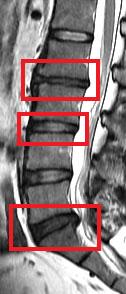

The current study was a cross-sectional assessment of adults from this cohort who were 21 years of age and older. A total of 2,599 individuals were assessed with magnetic resonance imaging (MRI). Amongst them, 27% (n=709) did not have disc degeneration while 73% (n=1,890) had. Of the subjects who have disc degeneration, 7% were underweight, 48% were in the normal weight range, 36% were overweight, and 9% were obese. Overweight and obese individuals were also found to have a greater extent and severity of disc degeneration in comparison to those individuals of normal weight or underweight.